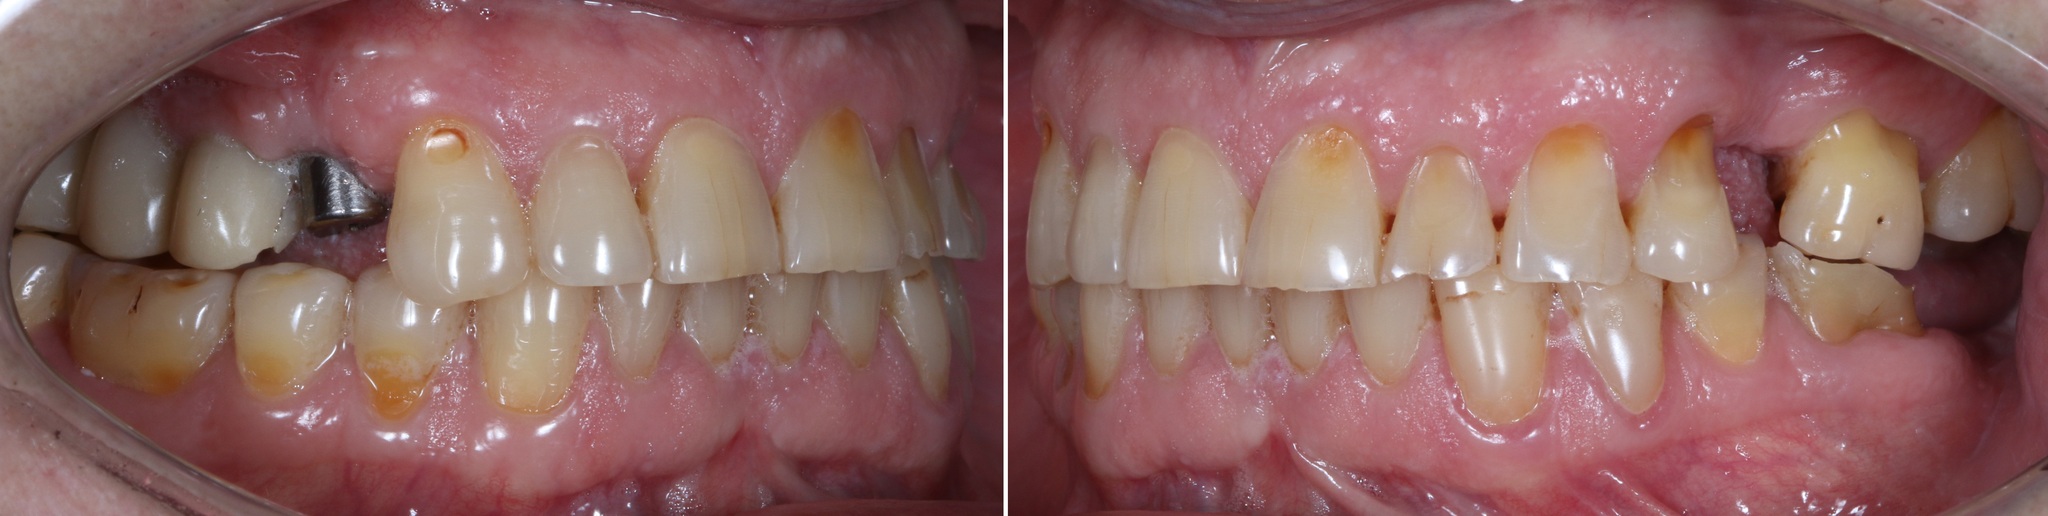

Январь 2024. Наши дни. Установка постоянных безметалловых коронок слева сверху:

Сканирование челюстей для изготовления ночной капы: